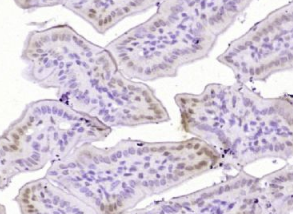

多聚甲醛固定,石蜡包埋(小鼠肠组织);用柠檬酸钠缓冲液(pH6.0)煮沸15min后获得抗原;用3%过氧化氢阻断内源过氧化物酶20分钟;阻断缓冲液(正常山羊血清)37℃30min;用(Bcl xL)抗体孵育THR115))多克隆抗体,未结合,1:400,4°C下过夜,然后根据SP试剂盒(兔子)说明和DAB染色进行操作。